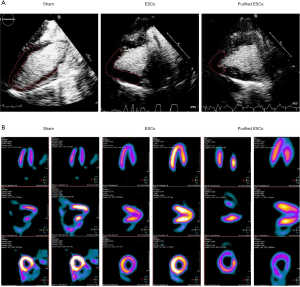

Local myocardial perfusion in the area of MI in each group was observed using MCE echocardiography (Figure S1). Compared with control group, the injection of stem cells in the treatment group (non-purified ESCs and purified-ESCs), the scope of perfusion defects were reduced after treatment (Figure 3A). Myocardial nuclide metabolism imaging was used to evaluate the infarcted area and the number of cardiomyocytes in the infarcted area. After stem cell therapy, the infarct ranges of the normal and purified cardiomyoid ESCs were decreased and the viable myocardium in the infarcted area was increased (Figure 3B).

Contractile cardiac function was assessed by echocardiography. CSIs were compared between the groups, and no significant difference was found before injection (P=0.561). Similarly, the WMSI (P=0.146) and VMR (P=0.526) measurements were not significantly different between the groups prior to injection. After injection, however, in comparison to the control group, the non-purified ESC group recorded improvement in each measurement, with an even greater improvement in the purified-ESC group (Figure 4A,B,C). This trend was further evidenced in the analyses of ejection fraction (EF) (Figure 4D) and the left ventricular end diastolic diameter (LVEDD) (Figure 4E), which also showed no significant difference between the groups prior to injection but an improvement in the ESC group and an even greater improvement in the purified-ESC group after injection.